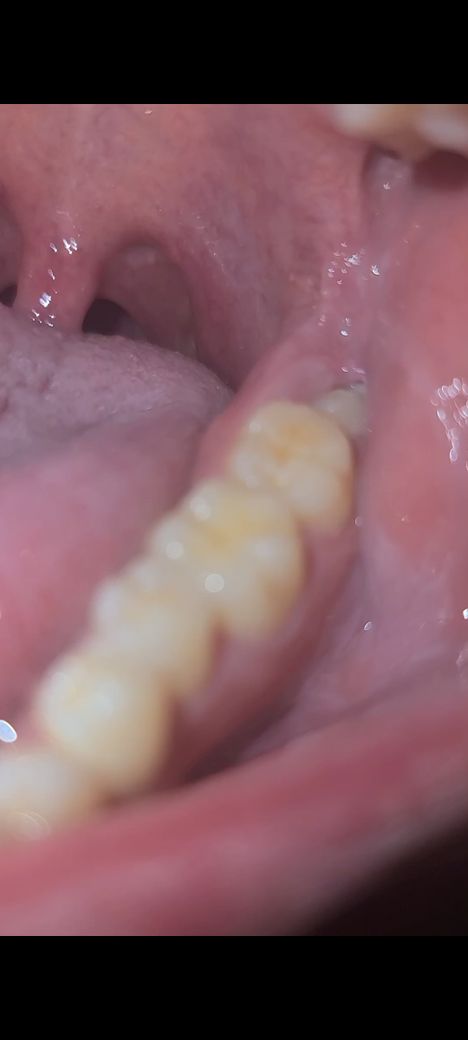

왼쪽 사랑니의 경우 반쯤 잇몸에 묻혀 있어 위생 관리가 쉽지 않아 충치나 잇몸병이 생기기 쉬우므로 미리 빼주는 것이 좋습니다

오른쪽 사랑니 보다 덜 누워있거나 매복이 덜 되어있는 경우 발치가 더 쉽습니다

사진 상으로 보았을 때는 결국에 문제를 일으킬 것으로 보입니다. 해당 사랑니 주변에 음식물이 쌓이면서 사랑니 뿐만 아니라 앞쪽 어금니도 손상시킬 것으로 보입니다. 따라서 치과 방문 후 발치를 하는 것이 좋습니다.